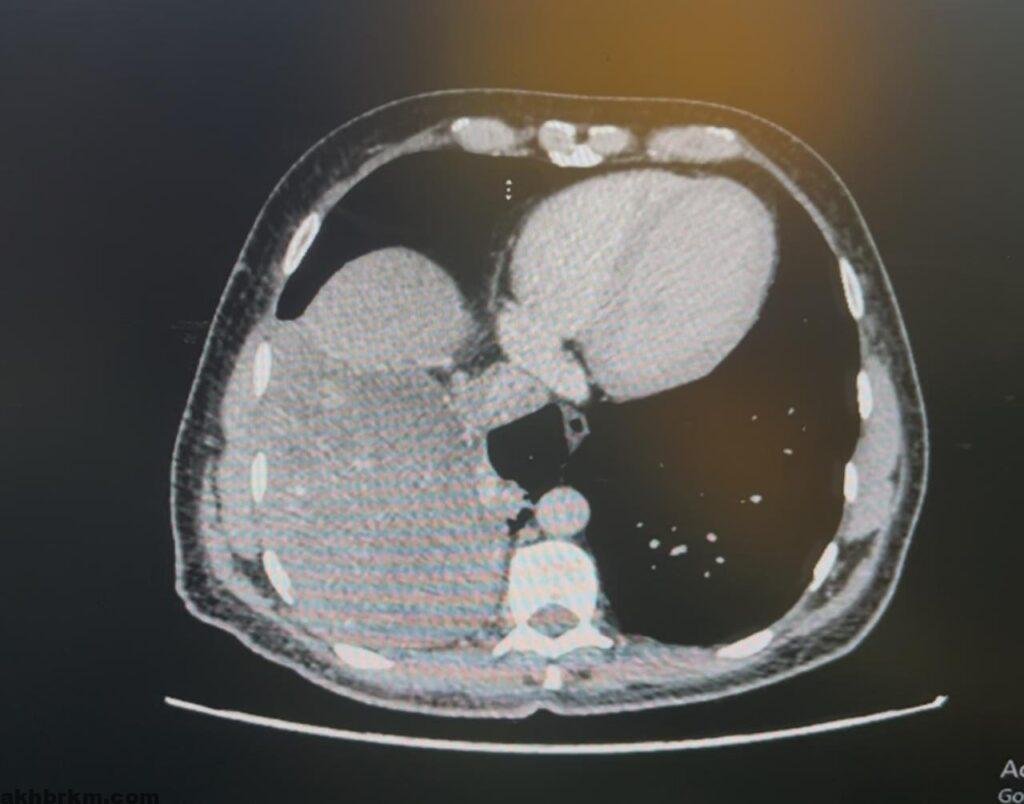

وكان المريض، البالغ من العمر 52 عامًا، قد راجع عيادات جراحة الصدر الخارجية بالمجمع وهو يعاني من أعراض مزمنة تمثلت في كحة مستمرة وارتفاع في درجة الحرارة. وبعد إجراء الفحوصات الطبية والأشعة المقطعية، تبين وجود ورم كبير يغطي النصف السفلي من تجويف الصدر، وملتصق بالفص الأوسط والسفلي من الرئة والحجاب الحاجز، ويلامس الوريد الأجوف السفلي الواقع أسفل القلب، مما زادت درجة الخطورة على حياته الصحية.